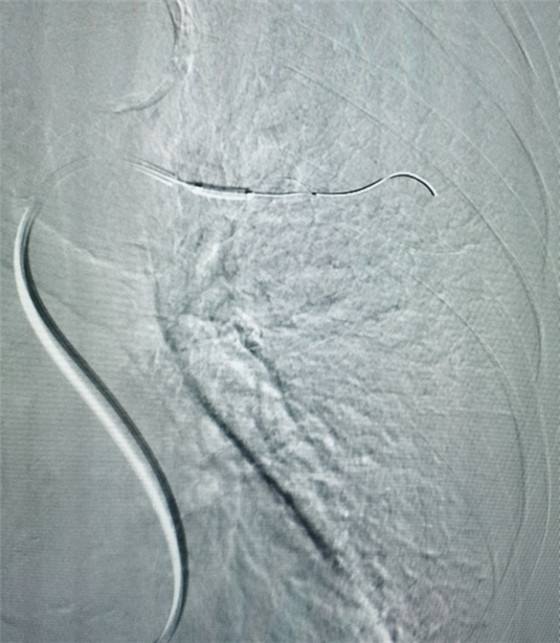

經(jīng)皮肺動(dòng)脈栓塞導(dǎo)管碎栓溶栓術(shù)

經(jīng)綜合評(píng)估并與家屬充分溝通后,局麻下行肺動(dòng)脈造影,提示左肺動(dòng)脈主干及左肺下葉動(dòng)脈閉塞,立即予以經(jīng)皮肺動(dòng)脈栓塞導(dǎo)管介入碎栓溶栓術(shù)。在心內(nèi)科韋鋒主任、郭良玉主治醫(yī)師及成婷護(hù)師的默契配合下,爭(zhēng)分奪秒順利完成手術(shù)。術(shù)后即刻復(fù)查肺動(dòng)脈造影示左肺動(dòng)脈主干及左肺下葉動(dòng)脈恢復(fù)血流,生命體征穩(wěn)定,指脈氧恢復(fù)至100%。經(jīng)過(guò)精心治療與護(hù)理,目前患者已康復(fù)出院。